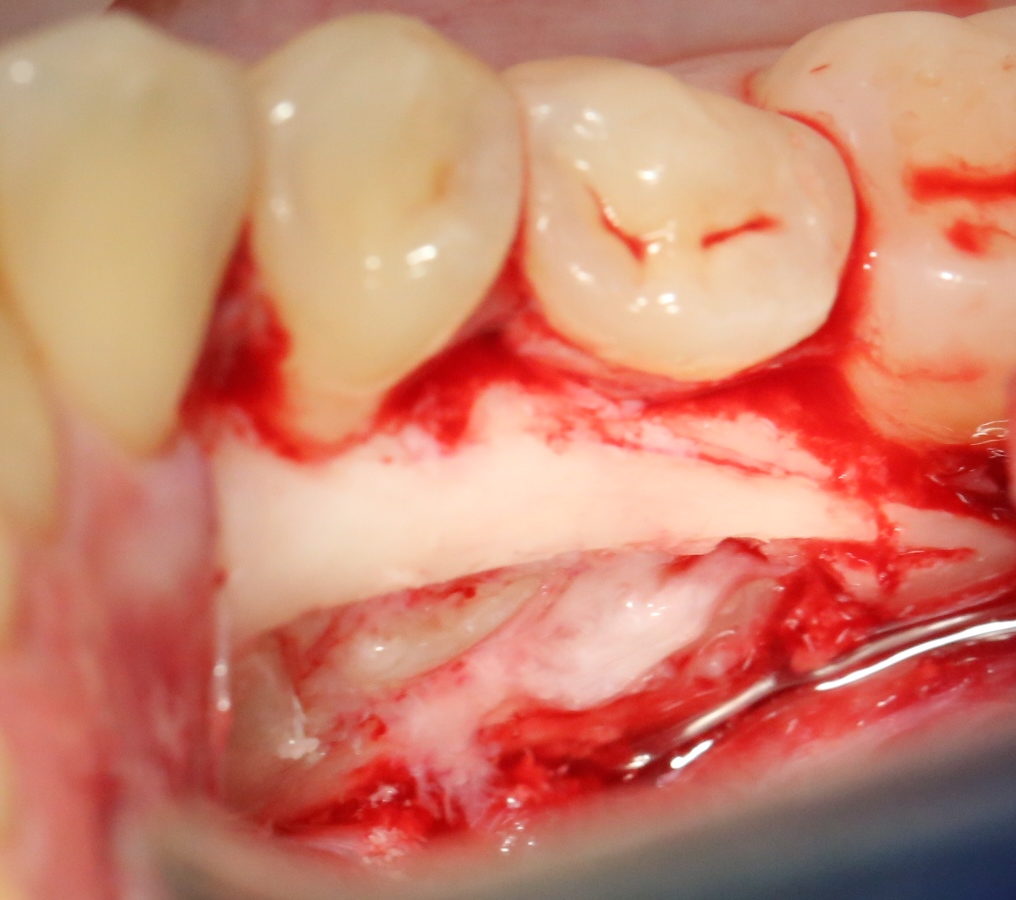

А вот их лунки:

Теоретически, лунки можно чем-нибудь заполнить. Только чем? И для чего?

Костная ткань сама регенерирует, если ей не мешать. Поэтому не стоит толкать в лунки какой-нибудь остеопластический материал, типа Cerabone или Bioss. Нет смысла.

В данном случае я использовал обычную коллагеновую губку — и то, только для того, чтобы «костная дверца», которую я выпилил в самом начале операции, не провалилась внутрь:

Теперь запиливаем «костную дверцу» на ее законное место:

И накладываем швы.

Благодаря сделанному нами разрезу, мы можем вывести узелки на внешнюю сторону альвеолярного отростка, что будет удобнее и комфортнее для пациента: